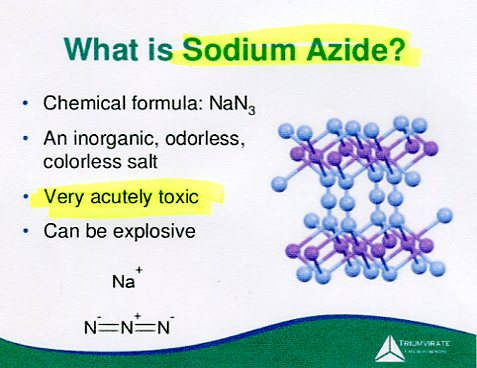

Serious issues with chemicals in at-home COVID tests

watch Carcinogenic EO in swab up nose & mask on face

watch How to use deadly NaN3 self-test COVID kit

News/YouTube, Jan 10, 2022